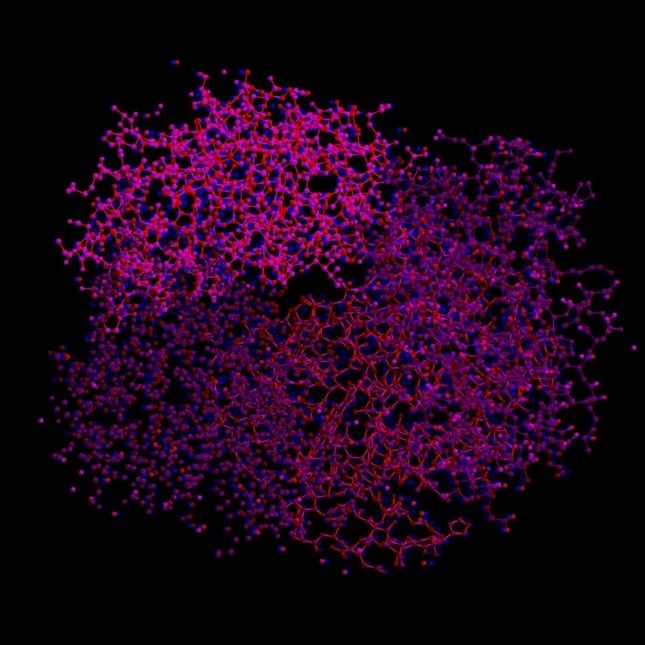

血红蛋白的分子结构